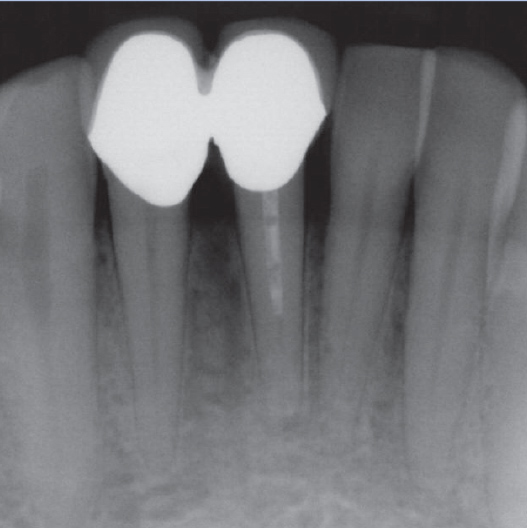

Before

After

Before Root Canal treatment

After Root Canal treatment